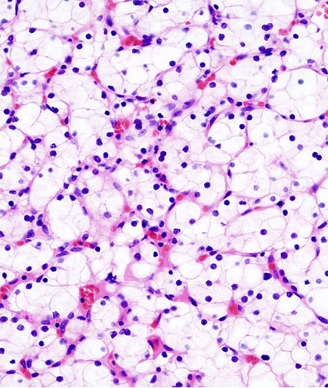

Histopathologic image of clear cell carcinoma of the kidney. Copyright 2005 KGH.